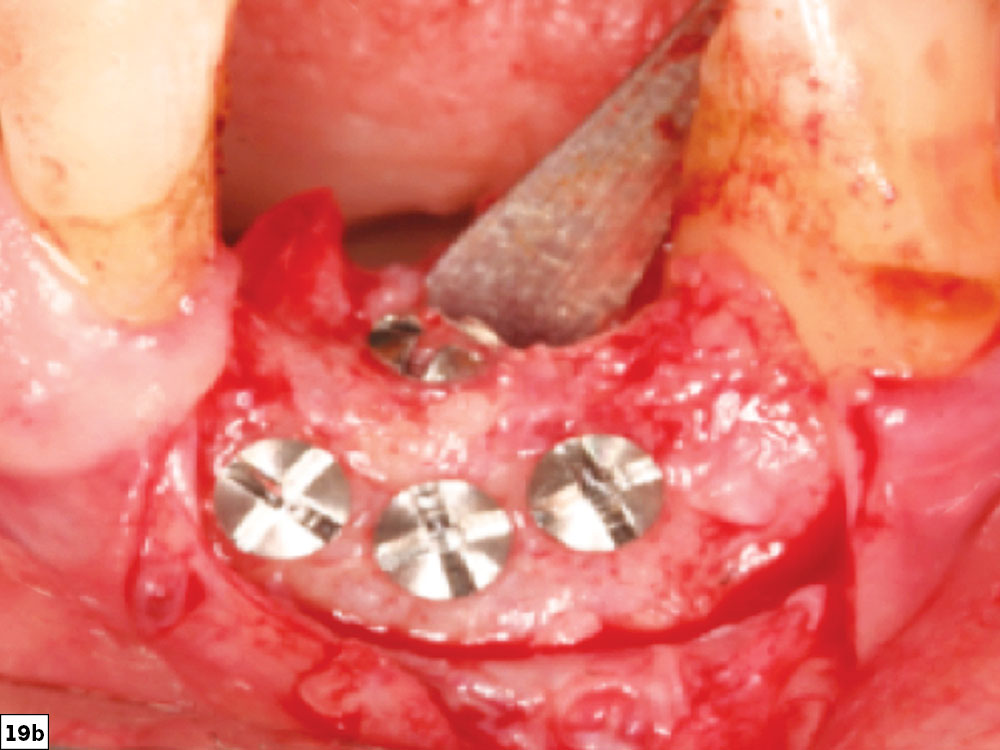

Vertical defect close-up

Horizontal and vertical bone growth to the level of adjacent teeth

Figures 19a, 19b: Very challenging vertical defect (19a) and final post-healing image depicting horizontal and vertical bone growth to the level of the adjacent teeth (19b).